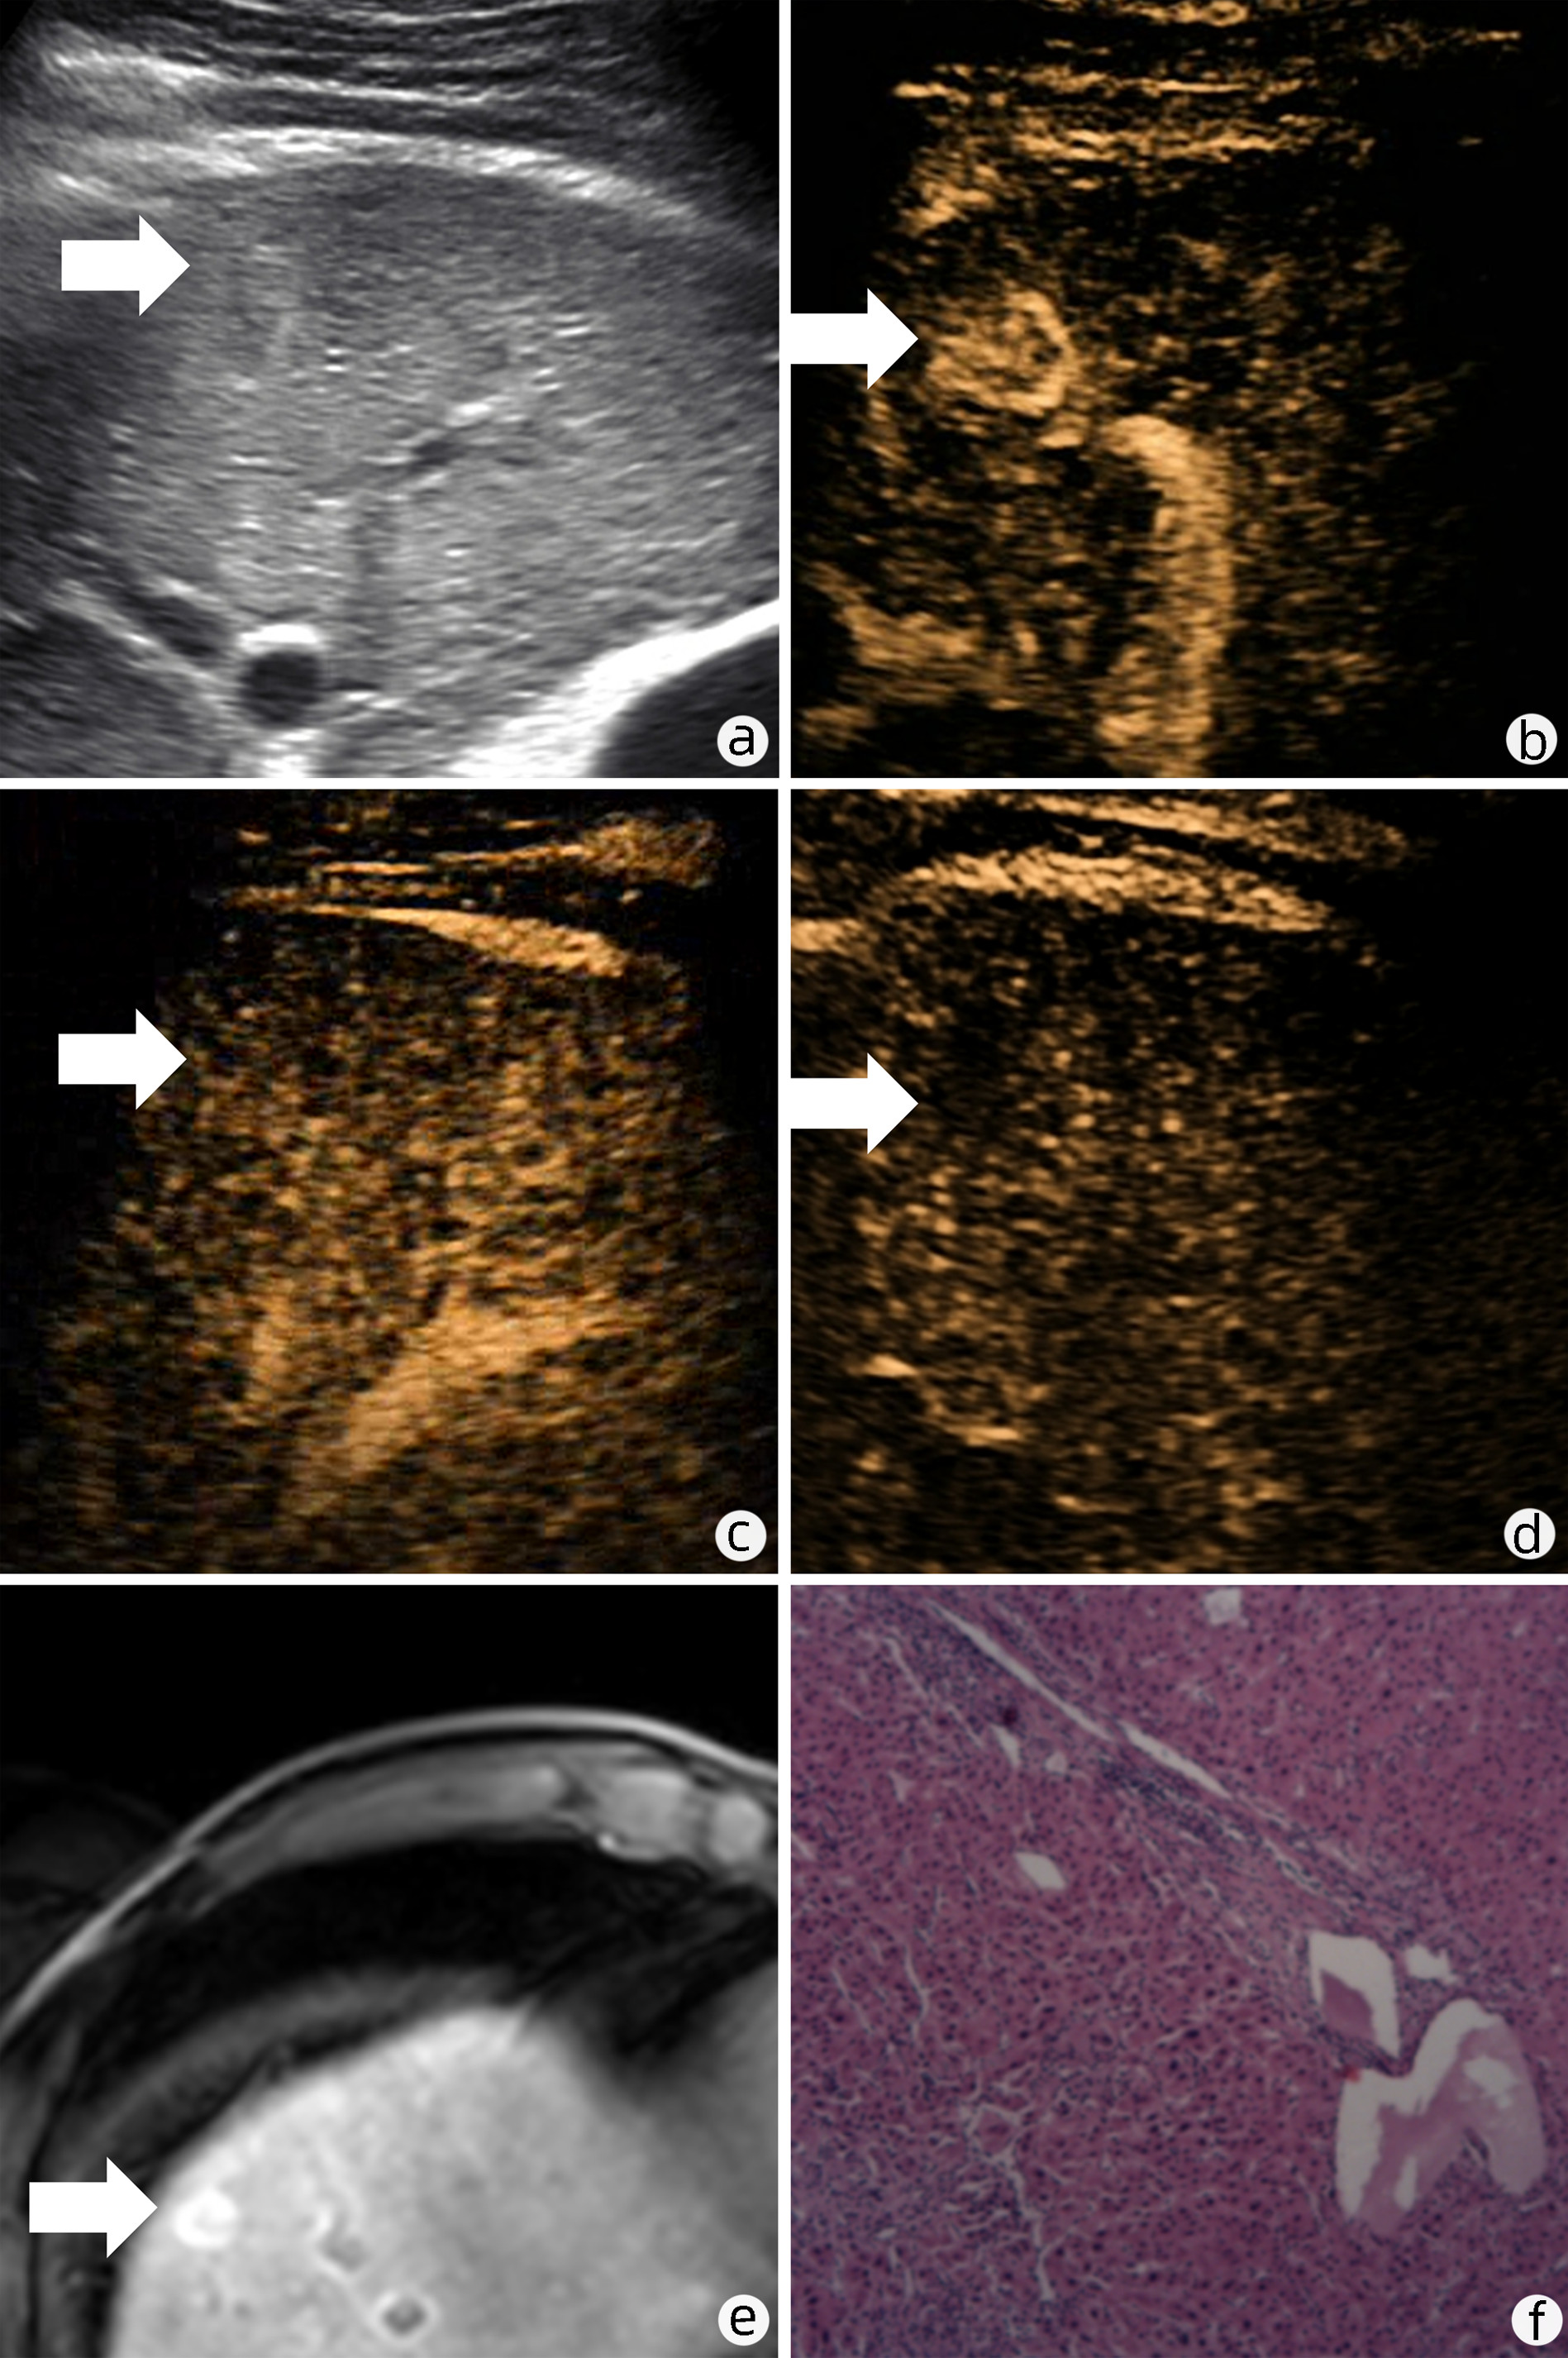

Focal nodular hyperplasia-like nodules in liver cirrhosis: An imaging analysis of three cases

Zinan LI, Shaoshan TANG, Xingni WU, Xiang LI

2023, 39(1): 142-146. DOI: 10.3969/j.issn.1001-5256.2023.01.021

Abstract(2471) HTML (2381) PDF (3394KB)(133)